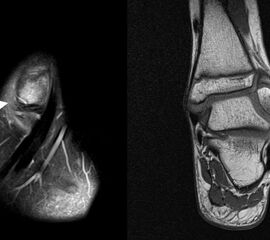

MRT

Die Kernspintomographie hat ihre Stärke in der Darstellung von Weichteilverletzungen. Insbesondere Verletzungen der Wachstumsfuge, des Periosts und der Bänder lassen sich gut visualisieren. Nachteilig ist die Untersuchungsdauer von 20-30 Minuten. Bleibt das Kind während dieser Zeit nicht ruhig liegen, kommt es zu Bewegungsartefakten, welche die Beurteilbarkeit der Bilder beeinträchtigen.

Os subfibulare

Multiple laminäre Ausrisse des fibularen Bandapparats aus der Fibulaspitze können zur Entwicklung eines Os subfibulare führen. Das Os subfibulare findet sich unterhalb der Fibulaspitze ventral der Peronealsehnen. Ohne Schmerzsymptomatik bzw. Aktivierung im MRT hat Das Os subfibulare keinen Krankheitswert. Ein mobiles Os subfibulare führt zu einer lokalen mechanischen Reizung teilweise in Verbindung mit einer Instabilität des Sprunggelenks. Im MRT zeigt sich eine Aktivierung des instabilen Areals. Bei anhaltenden Schmerzen besteht die Behandlung in einer operativen Entfernung des Knochens mit Refixation des Kapselbandapparats.